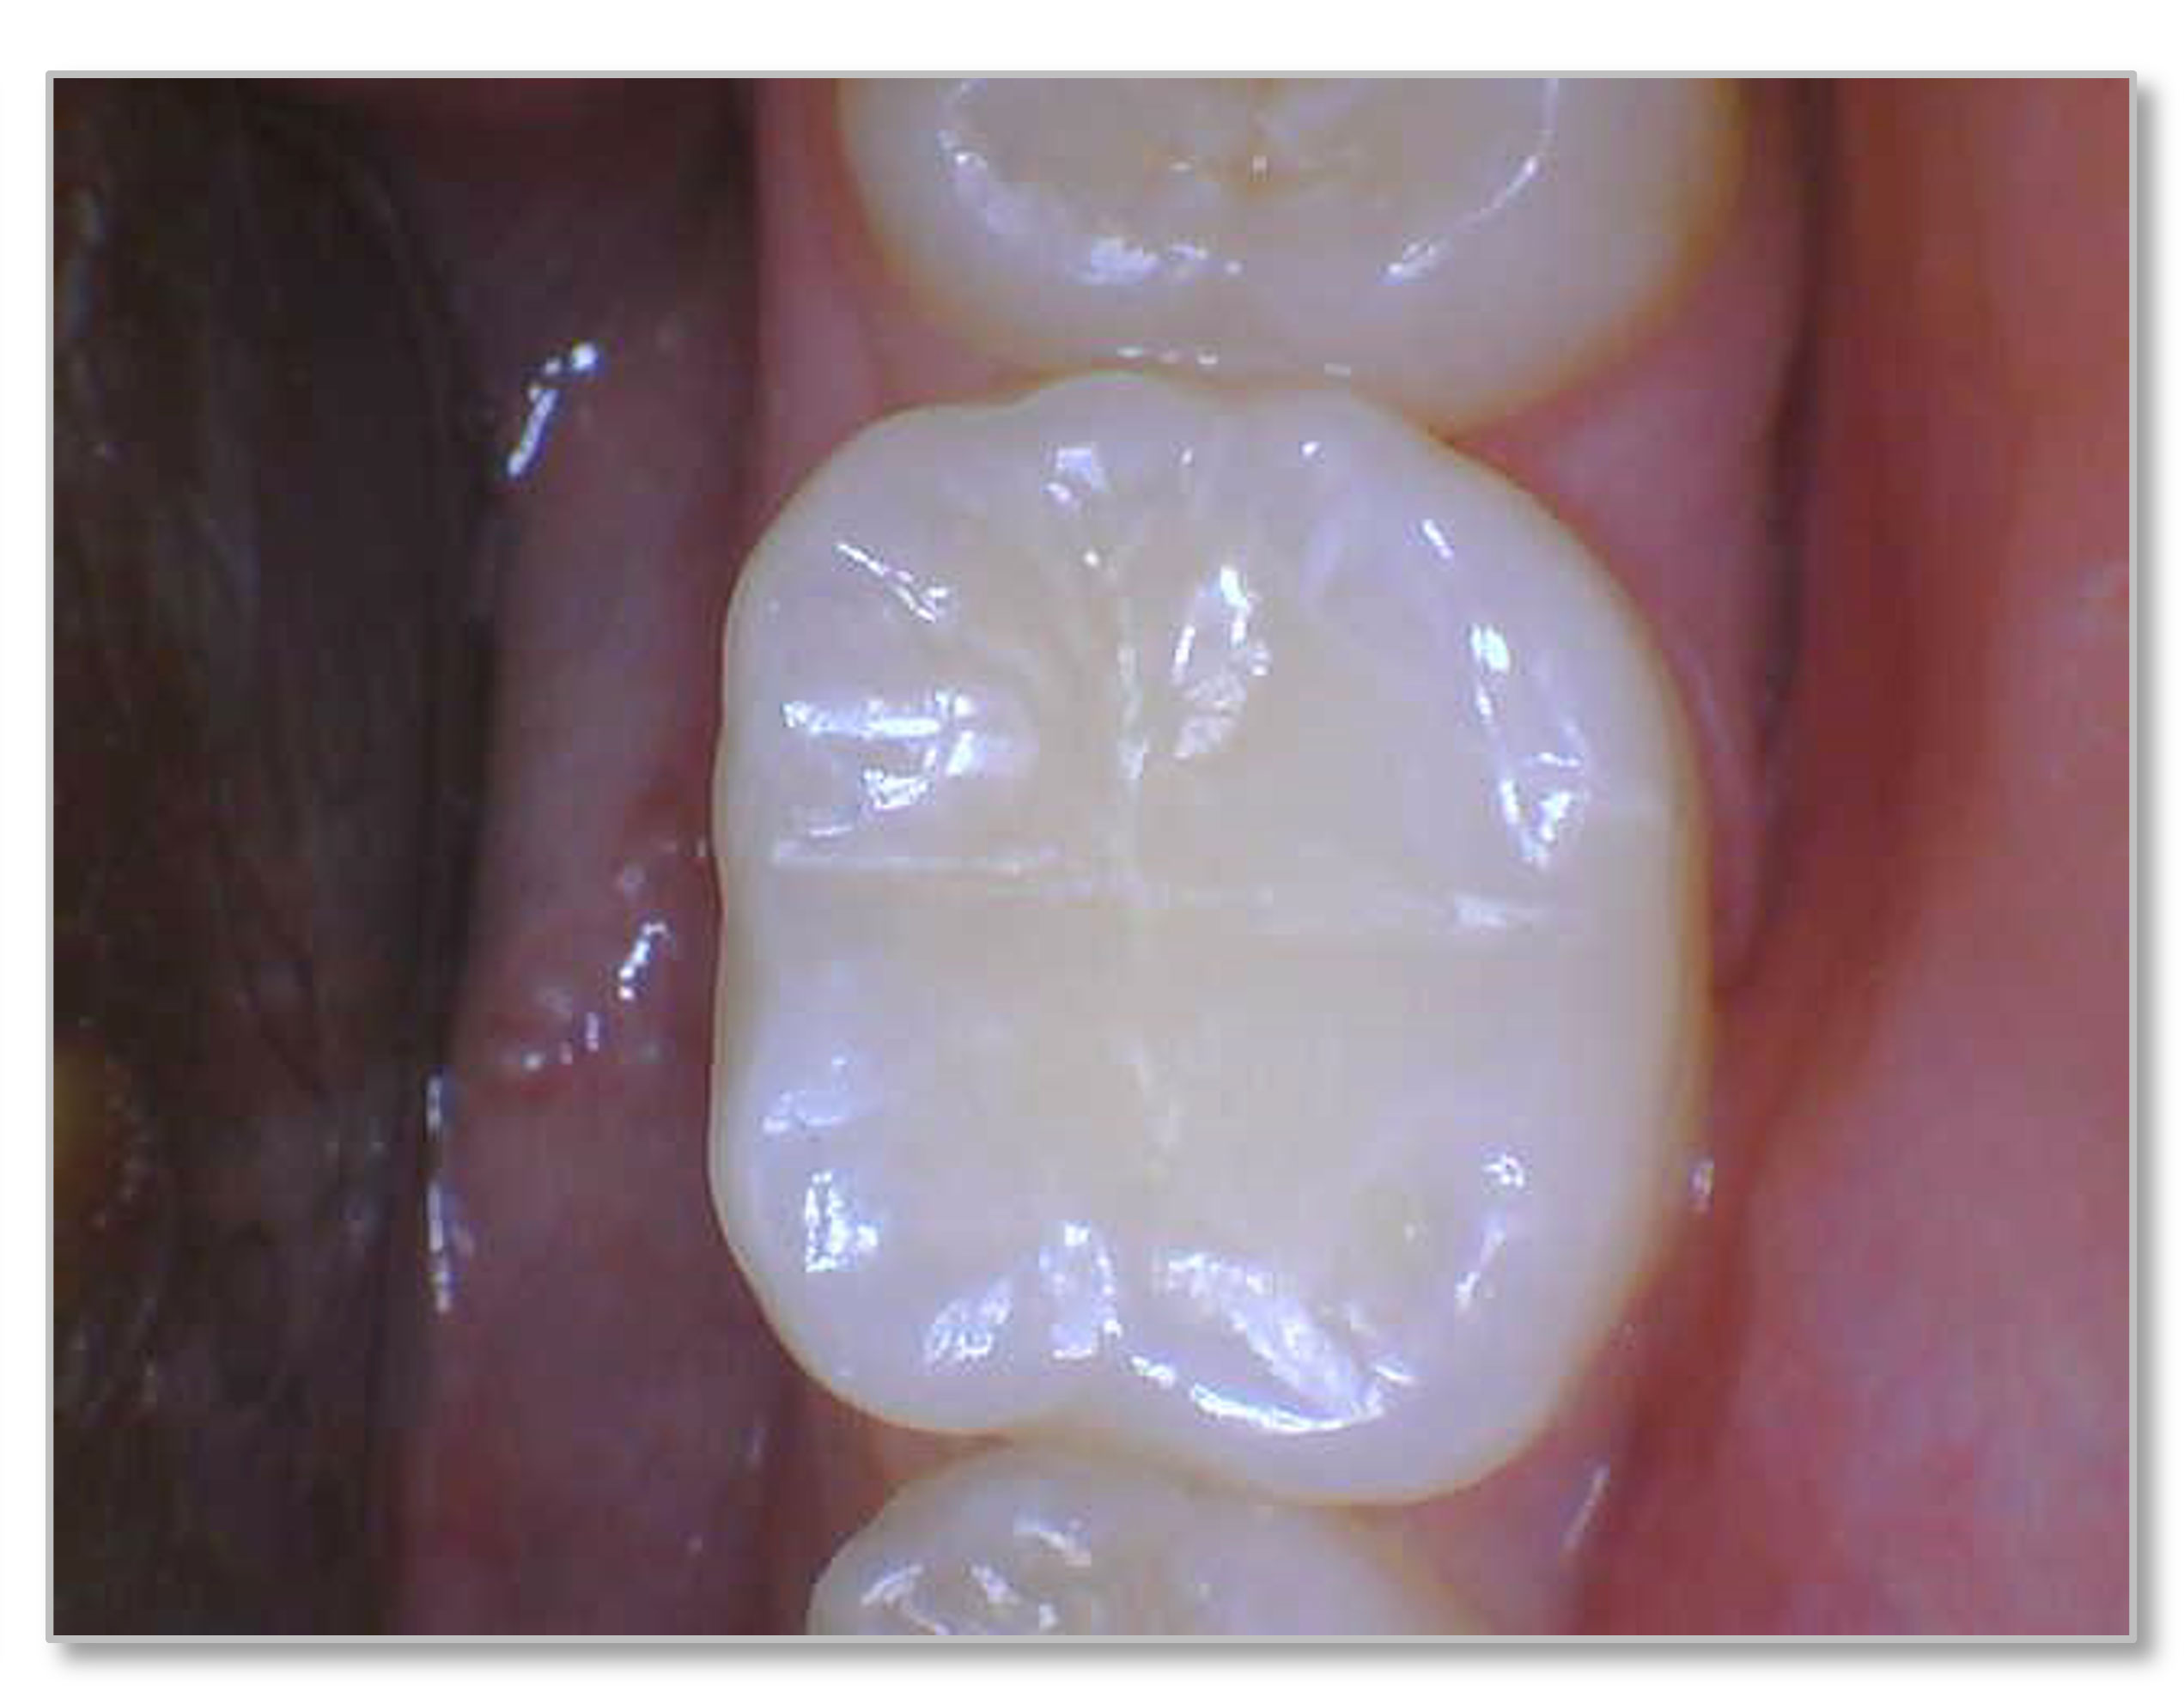

Figure 6a through Figure 6d show a procedure using a bulk fill packable as an interproximal Class 2, without using a bulk fill flow and not done with the snowplow technique to see how well the composite adapted to the margin. A light curable resin-modified calcium silicate liner (Bisco TheraCal LC) was used to perform an indirect pulp cap. A packable bulk fill composite was applied as a single increment layer to successfully restore the tooth. The material (Kerr SimpliShade Bulk Fill Packable) provided good adaptation to the tooth without gaps or polymerization stress lines and demonstrated great polishability and blendability. The patient reported no post operative sensitivity or discomfort in the 9 months after the restoration was performed. Sensitivity can be a concern if a composite is subjected to too much polymerization shrinkage.

Fig 6a. A procedure using a bulk fill packable as an interproximal Class 2, without using a bulk fill flow and not done with the

snowplow technique. A light curable resin-modified calcium silicate liner (Bisco TheraCal LC) was used to perform an indirect pulp cap. A

packable bulk fill composite was applied as a single increment layer. The material (Kerr SimpliShade Bulk Fill Packable) was used to provide

good adaptation to the tooth without gaps or polymerization stress lines and demonstrated great polishability and blendability.

Fig 6a. through 6d. A procedure using a bulk fill packable as an interproximal Class 2, without using a bulk fill flow and not done with the